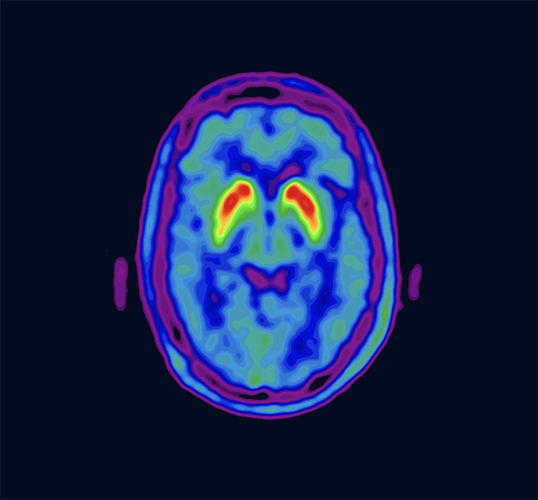

Vizamyl is indicated for positron-emission tomography (PET) imaging of the brain to estimate β-amyloid neuritic plaque density in adult patients with cognitive impairment who are being evaluated for Alzheimer's disease and other causes of cognitive decline.